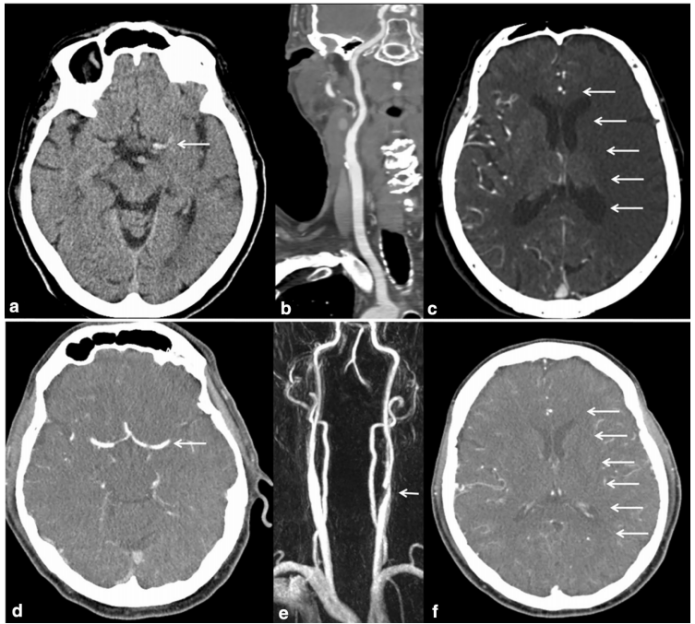

前循环大血管闭塞的卒中病因与侧支状态的关系